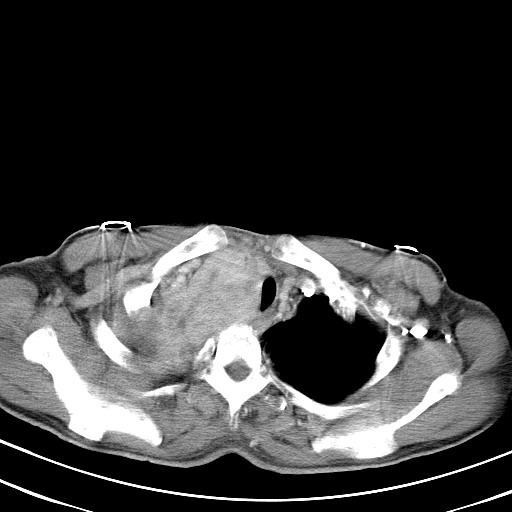

以下是引用汪涛同志在2007-8-2 0:40:00的发言:[br]病变虽然广泛,同时侵及双侧纵隔,但是无论左侧和右侧上下观察都是与右侧颈部甲状腺相延续的,而且强化幅度基本一致,又同时具有恶性病变病变的某些特征:肿块过大且密度不均,部分层面与正常纵隔结构分界不清,结合病史已有两年,考虑:胸内甲状腺肿恶变可能。[br]